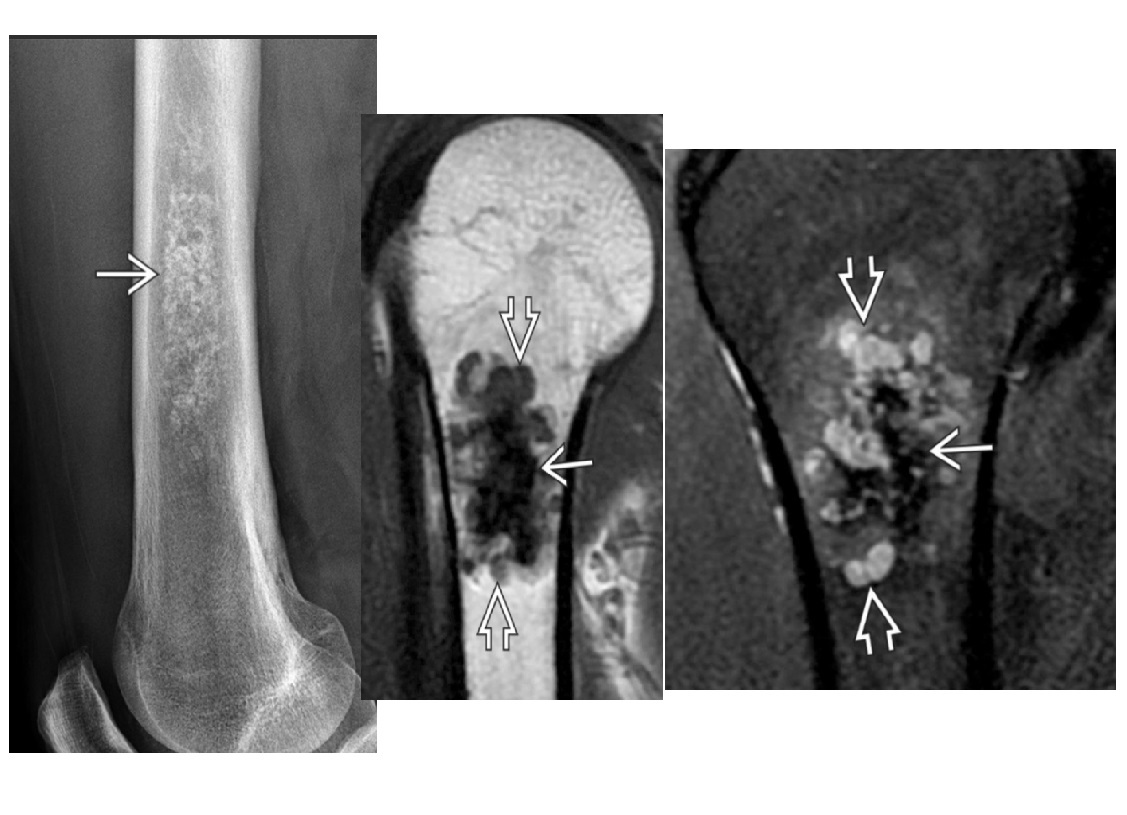

ENCHONDROMA

Commonest location Hands/feet

Long bones: proximal humerus > distal and proximal femur > proximal tibia

Intramedullary and metaphysis

multiple enchondroma

Maffuci - haemangioma

Olliers - multiple enchondroma only

DDx

-Brown tumor (hyperparathyroidism),

-sarcoid - lace like bone lesion phalanges

-intraosseous ganglion

-metastatic disease.

MRI

T1: low to intermediate signal

Fluid-sensitive sequences: lobulated high signal typical of cartilage lesions

Enhancement: peripheral and septal, accentuating lobules